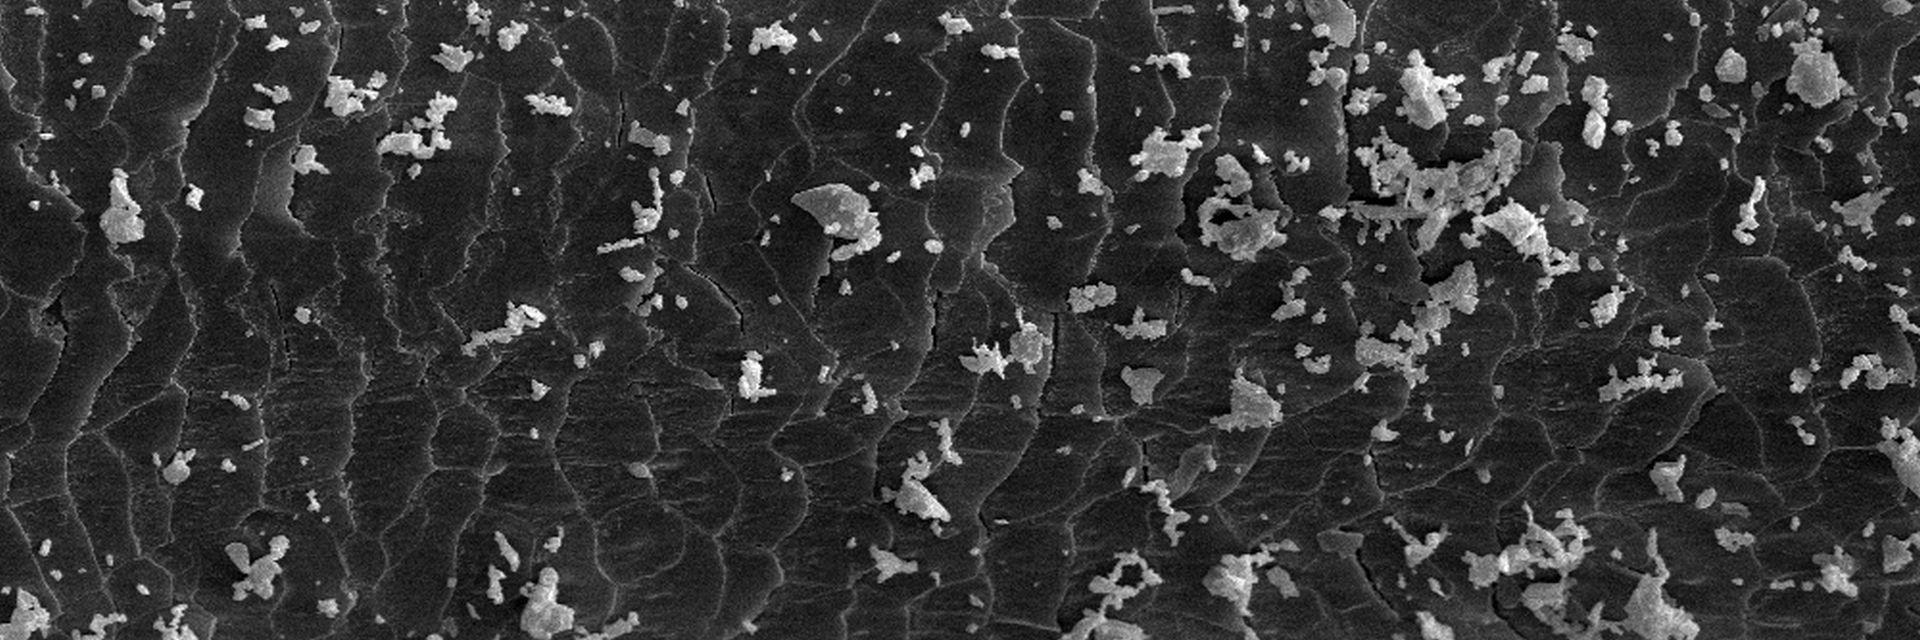

Microscopy Services setzt das patentierte Analyseverfahren Lipbarvis® (Lipid Barrier Visualisation, LBV) ein, um die epidermale Hautbarriere direkt ohne invasive Probenahmen untersuchen zu können.

Einleitungsteaser Anti Pollution Einleitungsteaser Anti Pollution Einleitungsteaser Anti Pollution Einleitungsteaser Anti Pollution Einleitungsteaser Anti Pollution Einleitungsteaser Anti Pollution Einleitungsteaser Anti Pollution Einleitungsteaser Anti Pollution Einleitungsteaser Anti Pollution Einleitungsteaser Anti Pollution Einleitungsteaser Anti Pollution.